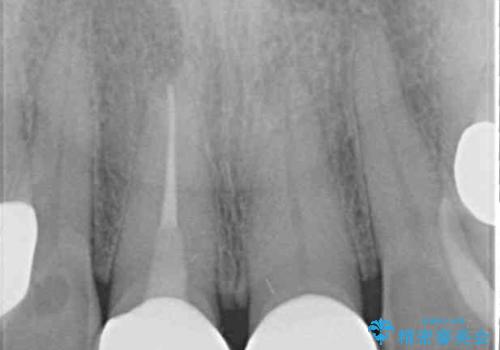

神経は残せていましたが、歯の色の変色が著しく、また広がった大きな形をしていたため、前歯2本をオールセラミッククラウンにて補綴することとしました。

前歯2本を同時に処置したことにより、色合いも形態もバランスの取れた仕上がりとすることができました。